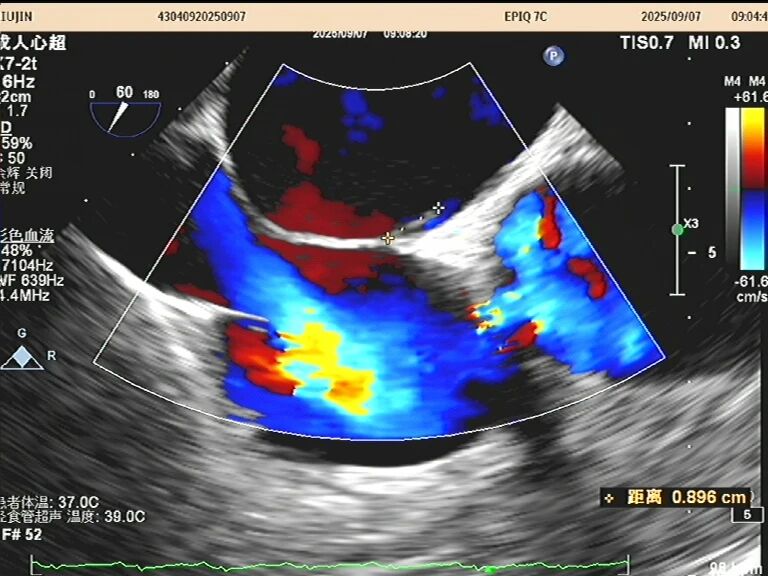

于是,一根如面条般柔软、顶端带着微型摄像头的探头,会从您的口腔缓缓进入食道。这个位置堪称完美,探头能紧贴着心脏,利用超声波为其拍摄一场无死角、超高清的“内部直播”。以前藏在背后的细微结构比如心耳里是否藏有血栓、人工瓣膜是否严丝合缝、心脏瓣膜上的小赘生物,此刻都一览无余。